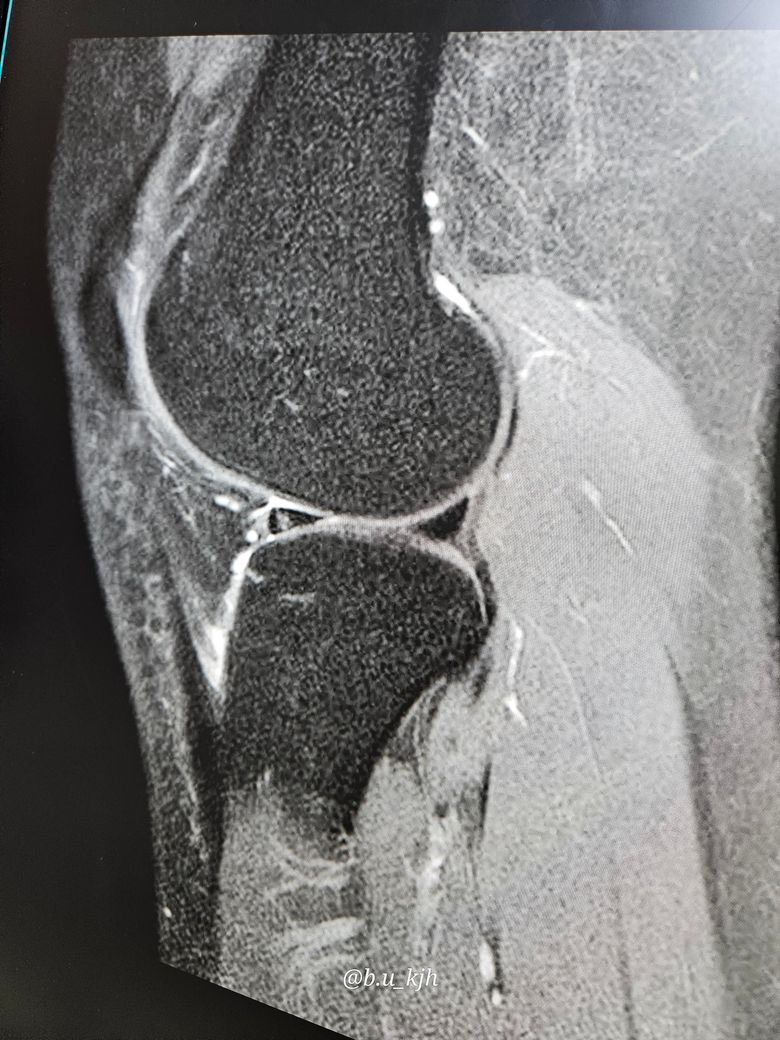

외측 연골판찢어짐이면 자연치유가 가능할까요?

병원에서 mri를 찍고 보니 오른쪽 연골판이 찢어졌다고 합니다. 의사가 말하길 외측 연골판 찢어짐

이라고 하는데 자연치유가 가능한가요??

• 1번 째 사진